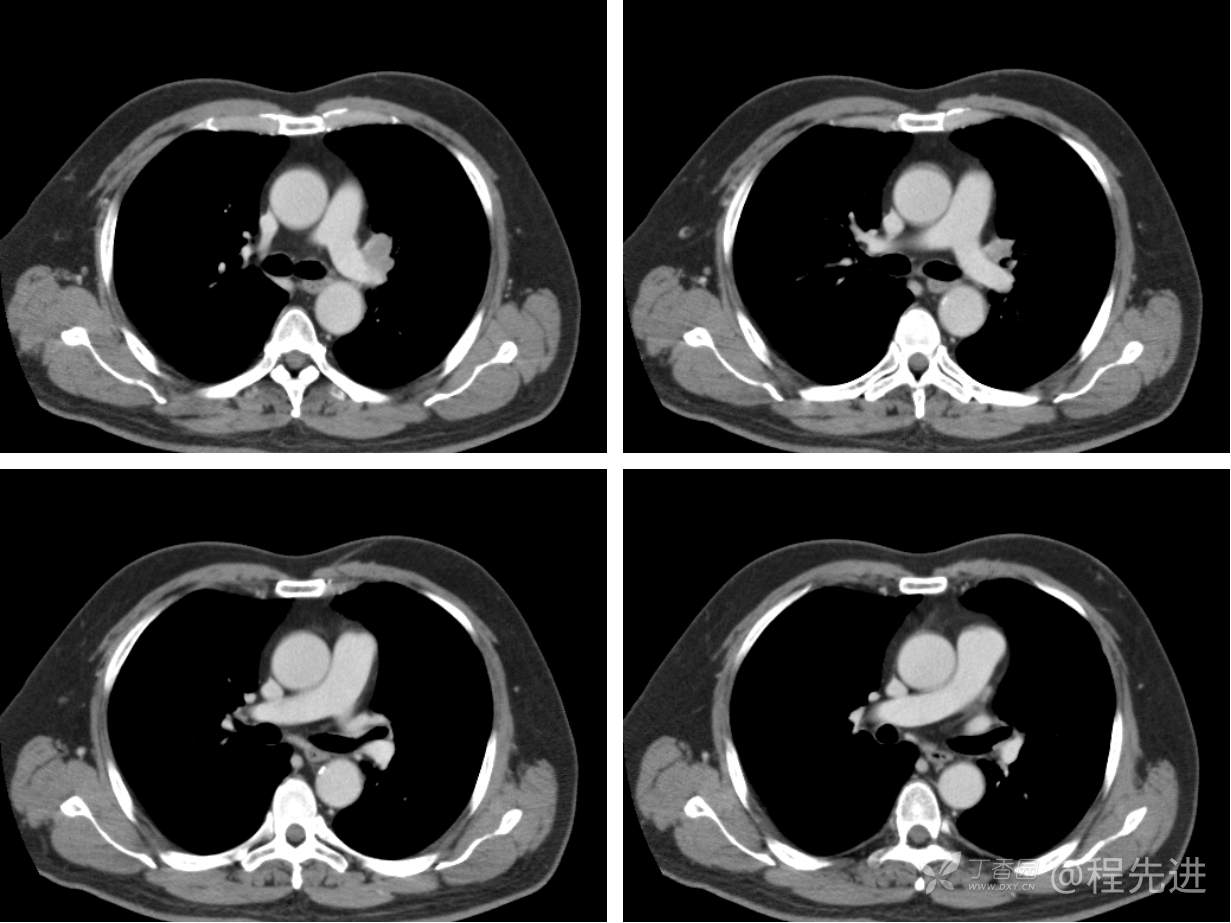

现病史概要:患者入院前约半月无明显诱因下出现咳嗽、胸闷症状,无明显发热症状,咳少量白痰,无明显咯血、喘息、头晕等不适,就诊我院查胸部CT示上纵膈肿物,左肺上叶支气管内肿物,现为行进一步治疗收入胸外科,患者近来饮食睡眠尚可,二便如常。